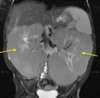

US Findings in ARPKD

Smoothly marginated

Enlarged

Echogenic

Loss of corticomedullary differentiation

In utero - may not see urine in bladder

XR findings in ARPKD

Wide Abdomen

Bilateral flank “masses”

Pulmonary hypoplasia